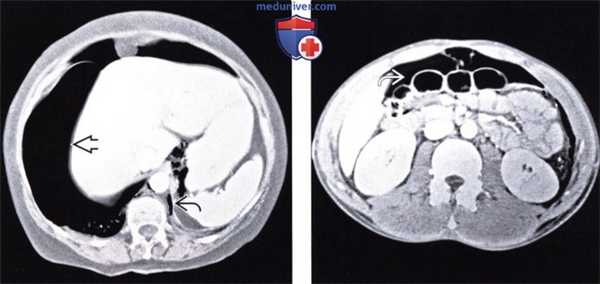

(Слева) При аксиальной КТ с контрастом у молодою человека, находящегося на ИВЛ после аварии на мотоцикле, выявлен напряженный пневмоторакс с правой стороны и малый пневмоторакс слева. Газ под давлением распространяется вдоль около-диафрагмальной жировой клетчатки.

(Справа) На аксиальном КТ срезе у этого же пациента визуализируется внепросветный воздух из грудной полости, распространяющийся в брюшную полость, очерчивающий контуры петель кишечника. Нет повреждения органов брюшной полости. (Слева) На аксиальном КТ срезе (с контрастным усилением) у пожилого пациента, находящегося на вентиляции легких под давлением, с документированным двухсторонним пневмотораксом и пневмомедиастинумом, визуализируется газ, распространяющийся под давлением в брюшную полость, забрюшинное пространство и брыжейку.

(Справа) На аксиальном срезе (КТ с контрастом) у этого же пациента в дополнение к обширному скоплению газа в забрюшинном пространстве визуализируется газ в брюшной полости. В подобных случаях газ может распространяться в кишечной стенке, симулируя пневматоз в результате ишемии.

(Справа) На аксиальном КТ срезе у этого же пациента визуализируется внепросветный воздух из грудной полости, распространяющийся в брюшную полость, очерчивающий контуры петель кишечника. Нет повреждения органов брюшной полости.

(Слева) На аксиальном КТ срезе (с контрастным усилением) у пожилого пациента, находящегося на вентиляции легких под давлением, с документированным двухсторонним пневмотораксом и пневмомедиастинумом, визуализируется газ, распространяющийся под давлением в брюшную полость, забрюшинное пространство и брыжейку.